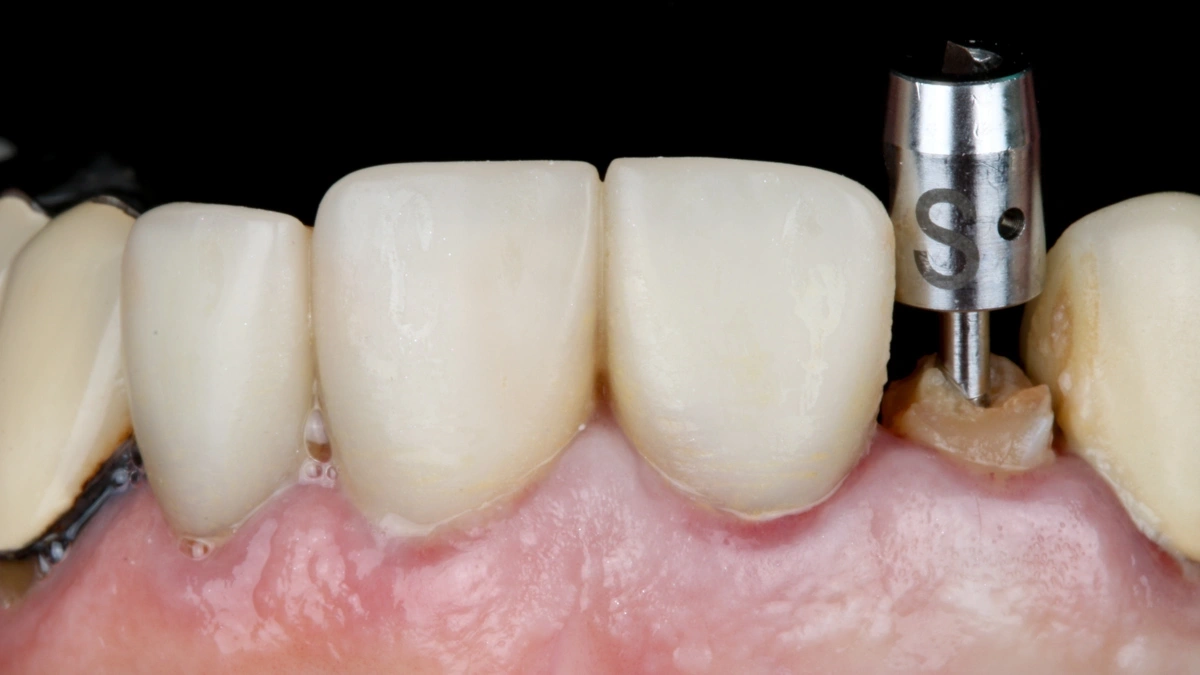

Las nuevas herramientas digitales, TAC 3D, cirugía guiada, planificación protésica virtual, han mejorado la precisión, pero no reemplazan la evaluación clínica. La ética consiste en usar la tecnología con criterio, no como argumento comercial.

En la práctica, la innovación está al servicio de la seguridad: cada planificación se revisa junto al estado sistémico del paciente antes de dar el paso quirúrgico. El objetivo no es colocar más implantes, sino asegurar que los que se coloquen funcionen de forma estable y saludable.